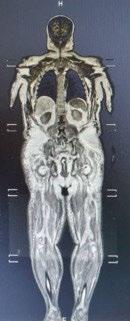

PETCT: interval reduction in metabolic activity at diffusely intense FDG uptake involving the axial and appendicular bones - good partial response

MRI & PET: Diffusely and focally hypermetabolic bone lesions in left 5th rib, both humerus, both scapulae, spines, both pelvic bones, both proximal fumora